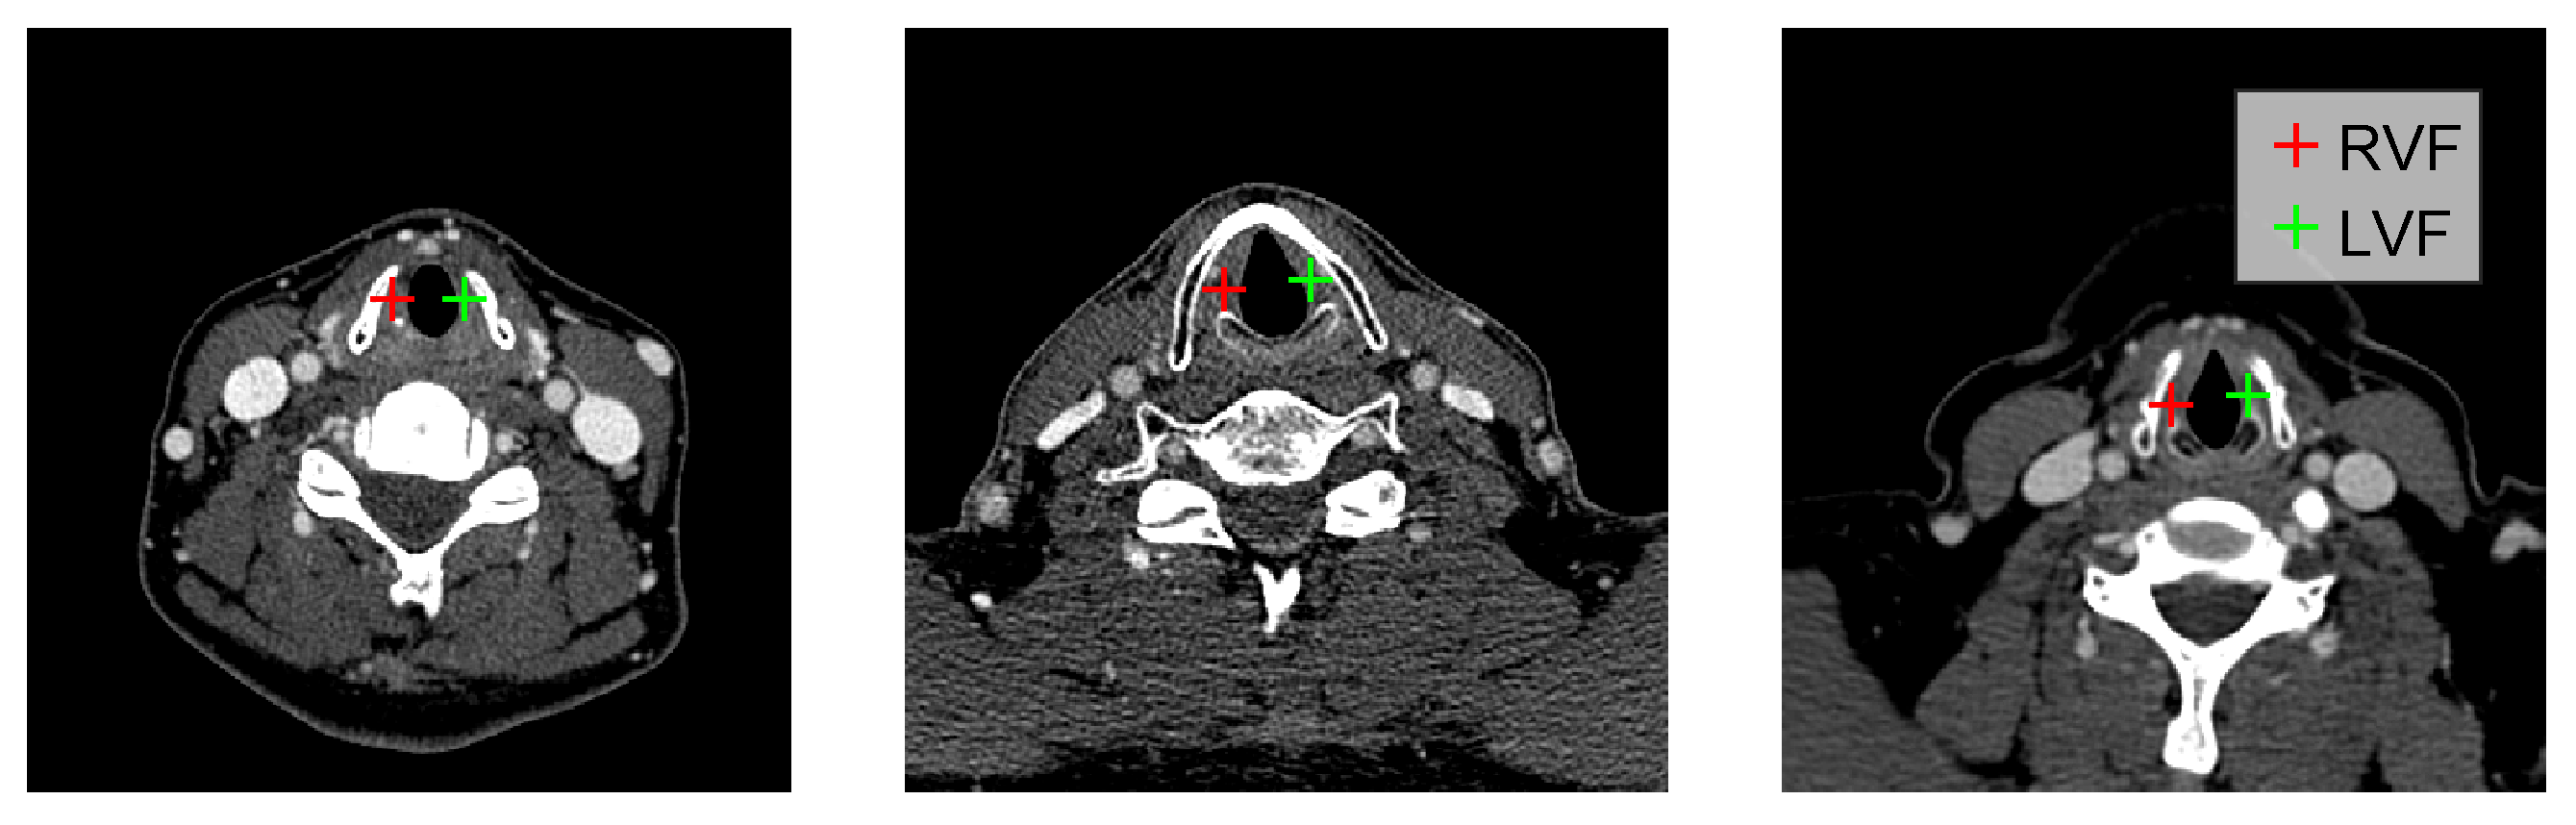

2. Methodology

Mirror Environment

3.1. Data

3.2. Evaluation Method and Performance Metric

3.4. Localization Performance